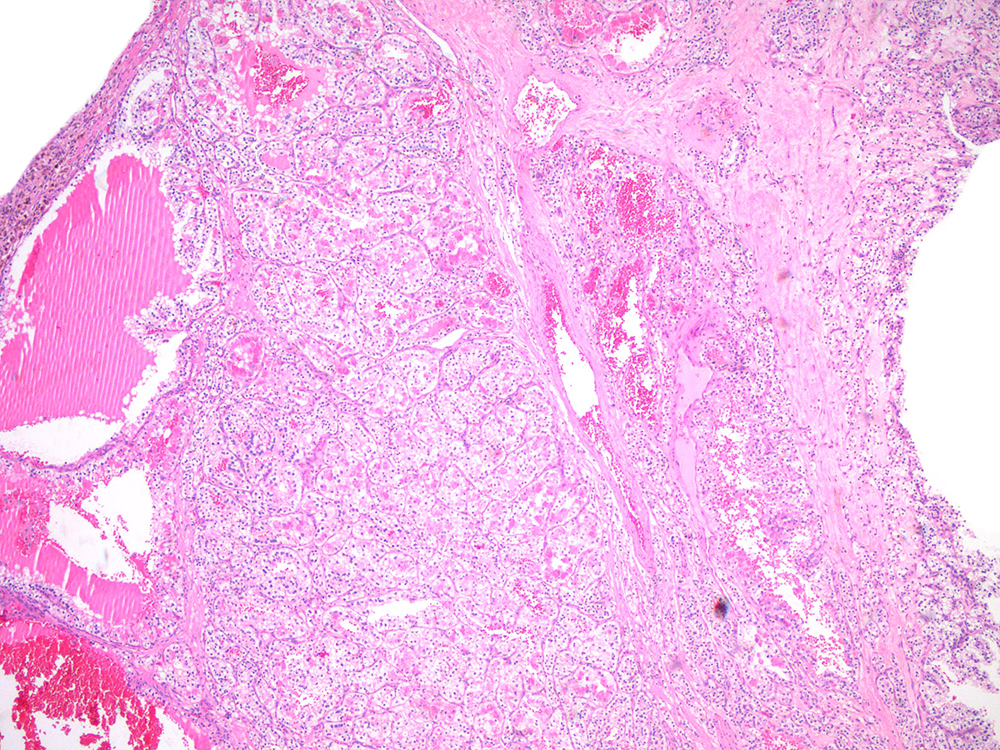

Classification of renal tumors

Case ID: 743